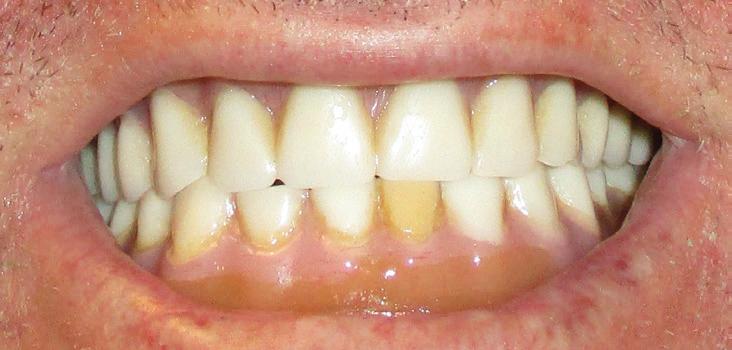

This patient is a 34-year-old male. He works as a dental assistant. His chief concern was, “I have temporary dentures that are six years old. They are discolored and do not fit well. I cannot eat with them.”

Implants were placed in areas of nos. 22 and 27. Implant no. 22 was Nobel Replace RP 4.3x11.5 torqued to 42.1 N/cm; implant no. 27 was Nobel Replace RP 4.3x11.5 torqued to 45.0 N/cm. Due to the patient wearing dentures, cover screws were placed and horizontal mattress sutures were placed. (The ends were clipped after the photos.) The patient was seen two days after and was healing well He was very happy with his treatment.